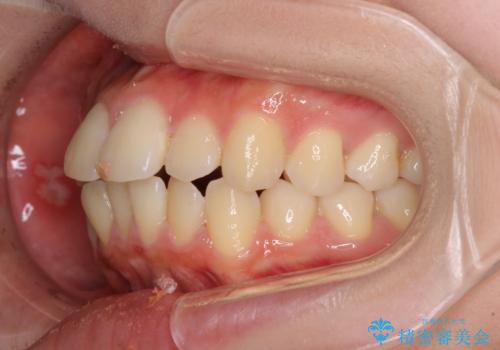

- 口元の閉じにくさを気にして来院された患者様です。

上下ともに歯列が前方に突出していたため、上下左右の第一小臼歯4本を抜去し、ワイヤー装置による矯正治療を行うこととしました。

舌の突出癖による影響もあったため、舌のトレーニングを並行して実施しました。